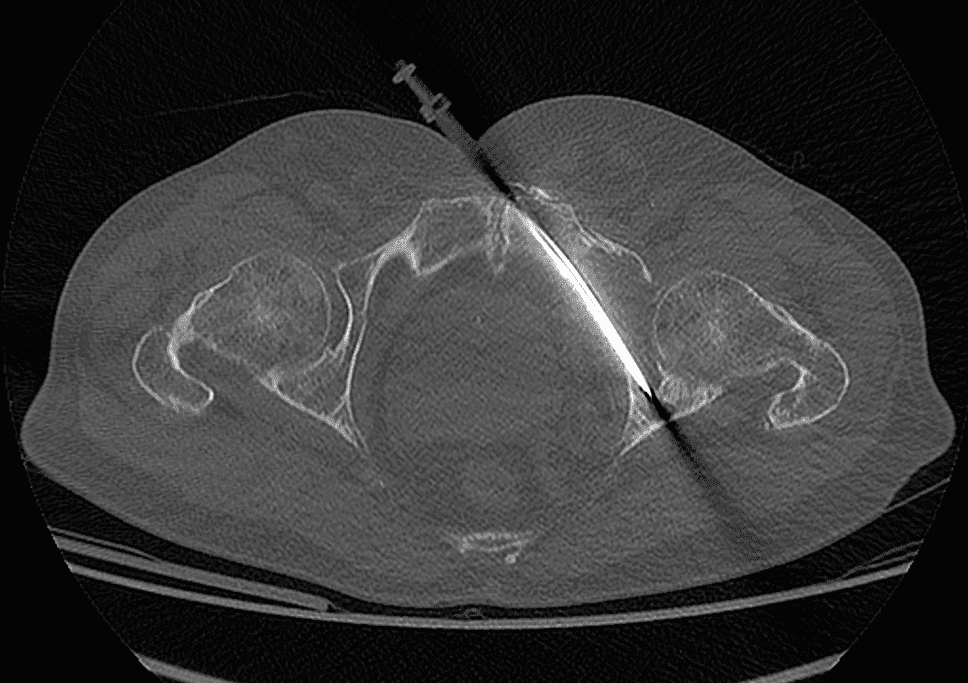

Sous anesthésie locale (parfois combinée à une légère sédation), une aiguille de guidage est introduite en se servant de la fluoroscopie pour vérifier en continu sa progression.

Insertion et déploiement du matériel d’ostéosynthèse :

Une fois l’aiguille positionnée, le vissage est réalisé en respectant la trajectoire prédéfinie, permettant de réaligner les fragments osseux.